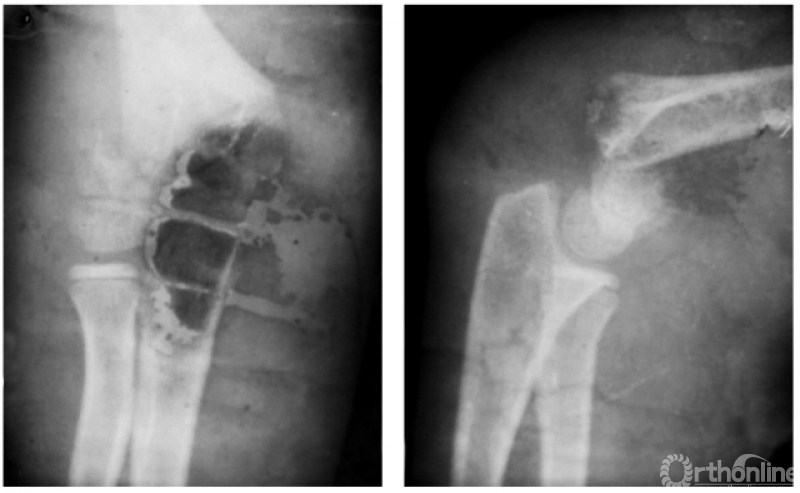

(一) 屈曲型

例:屈曲型兼桡偏,即远折端向前向内移位(图1)。

图1